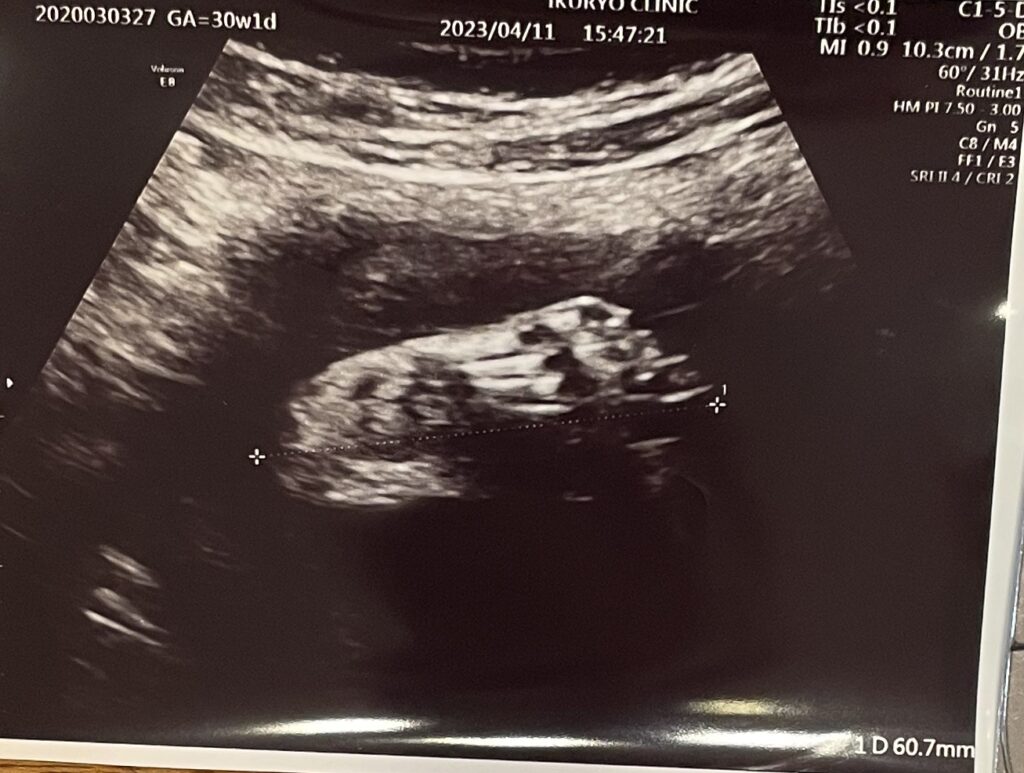

今日の経膣エコーでは、子宮頸管が短くなっていないかを見るとのことで、先生がエコーの器具を膣に入れた直後。

「ん?あれ?」と。

わたしは心の中で「え、なに?」とドキドキ。

先生が焦って笑いながら「さっき赤ちゃんの頭下だったんだよね?!」とわたしに聞くのです(T_T)

そう、なんと、待合室で待っていた15分程度の間に赤ちゃんが逆子になってしまったんです。笑

「そんなことある?!」と先生も笑いながら、経腹エコーで確認しようということになり確認しましたが、やっぱり頭が上になっていました〜。